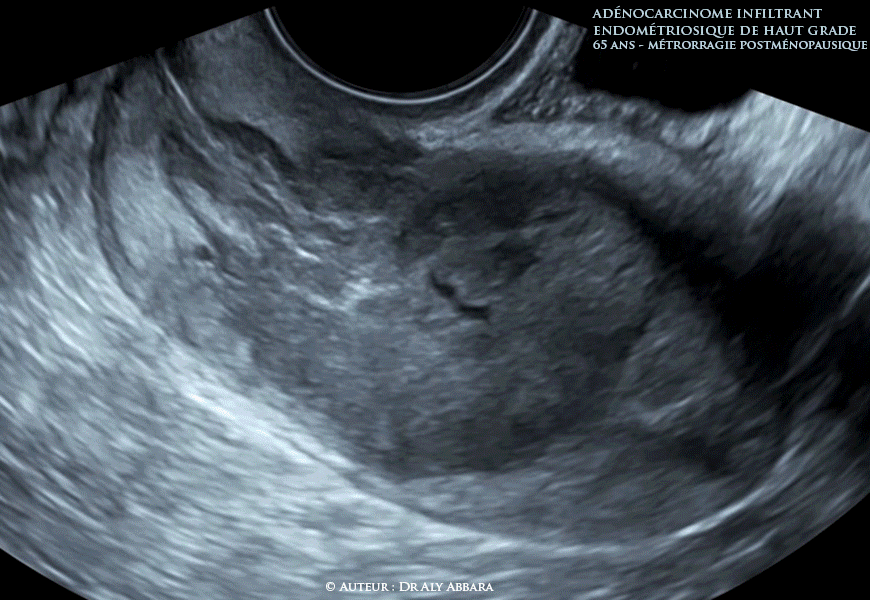

Utérus - Adénocarcinome endométroïde infiltrant de haut grade - Échographie

Utérus : un adénocarcinome endométroïde prenant l'aspect échographique d'une tumeur solide hypervascularisée de 46 x 29 x 30 mm de diamètres infiltrant plus 50% du myomètre sans dépasser la séreuse et étendue (échographiquement) vers le canal endocervical.

Biopsies de l'endomètre : il s'agit d'un adénocarcinome infiltrant endométriosique de haut grade.

• Il s'agit d'une patiente est âgée de 65 ans se plaignant depuis quelques semaines de métrorragies répétitives post-ménopausiques (non induites par un traitement hormonal substitutif).